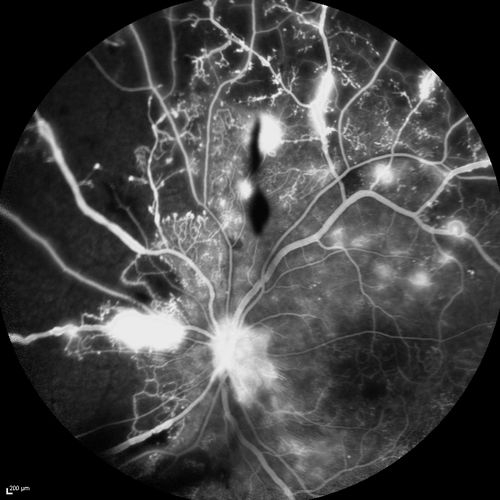

Proliferative Diabetic Retinopathy - Moderate - mild NVD with NVE

FA shows leakage from neovascularization and dark areas in periphery from non-perfusion